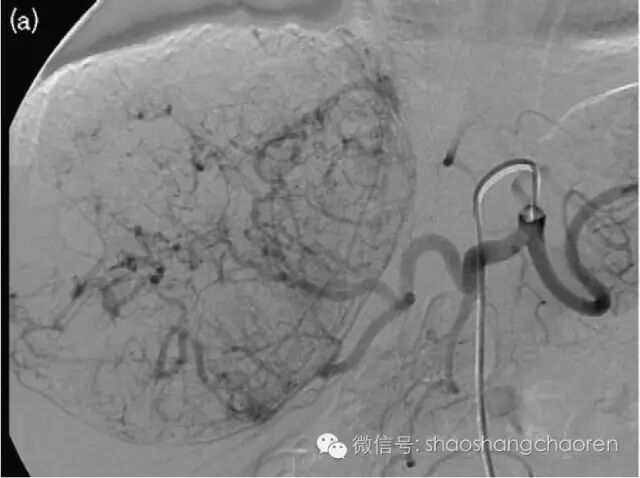

对于晚期肝癌,有一种常用的治疗方法,叫做动脉插管化疗栓塞术。这种手术的原理,就是在x线引导下,从外周血管将一根细细的导管插到肿瘤部位,将化疗药物注入肿瘤内,同时将肿瘤的供血血管栓塞,最大限度阻断肿瘤的血运,以达到杀死癌细胞缩小肿瘤的作用。

报道中医生的做法,是对传统动脉插管化疗栓塞方案的改良,在栓塞肿瘤血管和注入化疗药物的同时,将碳酸氢钠(也就是小苏打)同时注入肿瘤,以干扰肿瘤代谢,加强杀灭效果。这是一个很有益的尝试,目前看效果也不错。但由于样本量过小等原因,具体效果还需要进一步评估。

说白了,这个方案中,小苏打是在常规的动脉插管化疗栓塞的前提下起作用的。十几块钱的小苏打起作用的前提,是价格不菲的插管化疗栓塞手术。